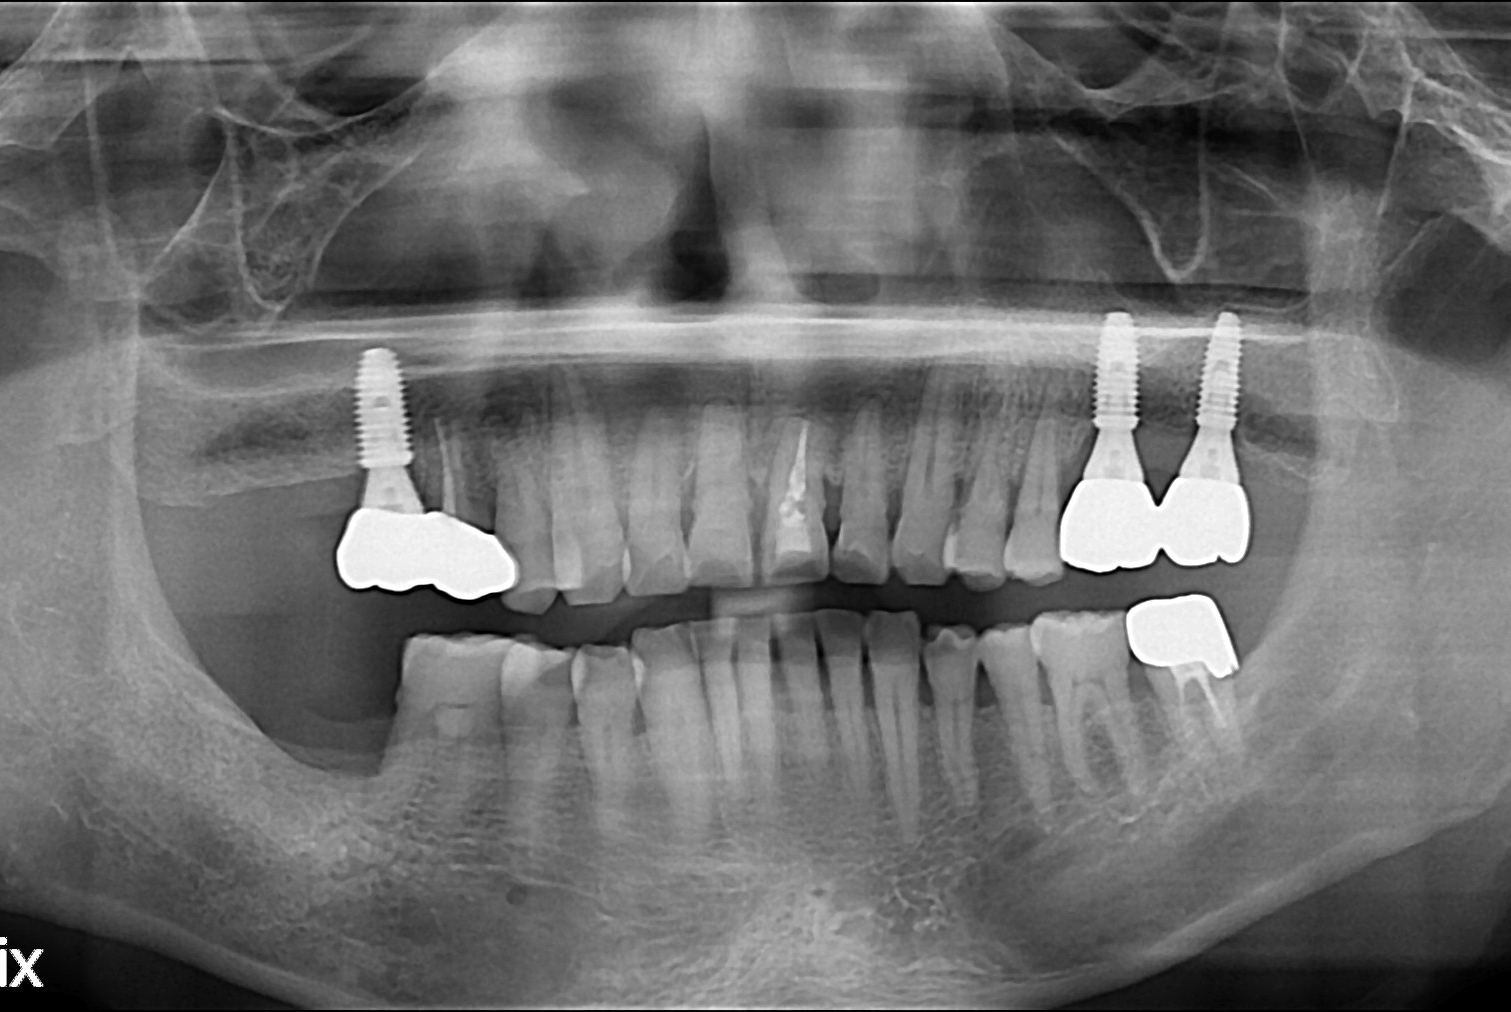

치료후 : 2019-08-09

세종치과는 많은 환자와 다양한 케이스를 바탕으로 항상 편안한 임플란트 수술을 제공하고자 노력하고,

오래동안 튼튼히 쓸 수 있는 임플란트 수술을 가장 큰 목표로 삼고 있습니다